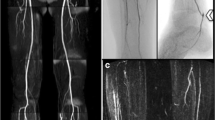

In a meta-analysis published in JAMA in 2009, 20 diagnostic cohort studies analyzed with 957 patients predominately presenting with intermittent claudication (68 %) showed that the overall sensitivity for CTA detecting more than 50 % stenosis or occlusion was 95 % (95 % CI, 92–97 %) and specificity was 96 % (95 % CI, 93–97 %), when compared to intra-arterial DSA [1] (Fig. 17.2). Understaging (underestimation of disease severity) occurred in 9 % of segments and overstaging (a significant stenosis was diagnosed by CTA as an occlusion) occurred in 4 % of segments. However, this meta-analysis only included one study with critical limb ischemia (CLI) patients, identifying the need for further evaluation in this population. In addition to lesion severity, CTA is also highly accurate in identifying length and number of lesions [2], as are required for correct treatment decisions per TASC guidelines, making CTA a valuable tool for therapeutic planning. More recent data with 64 slice CT scanning echoes previous studies, with 98 % accuracy for CT angiography detecting greater than 70 % stenosis, in a prospective cohort of 212 symptomatic PAD patients (acute CLI excluded) [3] (Fig. 17.3). It further suggested that results could be used to effectively guide clinical management, as therapy recommendations based on CT angiographic findings alone were identical to those based on DSA findings in all but one patient. Similar results can be found in a cohort of 41 patients with critical limb ischemia and severe claudication [4], making CTA a useful tool in treatment planning.

A 65-year-old male with known peripheral arterial disease, with a history of acute-on-chronic left lower extremity claudication, found to have stenosis of the right superficial femoral artery. (a) Magnified CTA-MIP showing severe stenosis of SFA mid-thigh with atherosclerotic plaque along its course. (b) DSA showing the same SFA stenosis

A 65-year-old male with HTN, DM, HLD presenting with LLE claudication and L common iliac stenosis. (a) CTA-MIP showing calcified plaque causing high-grade stenosis at the origin of L common iliac artery (inferior arrow). Also, note the presence of mural thrombus with calcification (superior arrow) in the distal abdominal aorta just above the bifurcation. (b) DSA demonstrating the same severe L common iliac stenosis (arrow)

Although DSA is used as a reference standard against which noninvasive imaging is compared, it has downsides as well, one limitation being two-dimensional imaging of a three-dimensional structure. The severity of an occlusion may be over- or underestimated depending on the angle from which the vessel’s image is acquired [9]. In a study comparing pre-amputation angiogram vs. post-amputation pathology, DSA tended to underestimate the severity of stenosis, plaque concentricity, and grading of calcification even in normal-appearing vessels [10]. Another drawback is DSA’s need for good contrast timing for visualization of the vasculature in satisfactory detail. This task may be difficult in assessing different bypass grafts given complex anatomy leading to poor contrast timing and suboptimal vessel opacification (Fig. 17.11). Compared with conventional DSA, the sensitivity and specificity of multi-detector row CT (MDCT) angiography in the detection of significant stenosis, aneurysmal changes, and arteriovenous fistulas of arterial bypass grafts were more than 95 % [11] (Fig. 17.12). Advances in MDCT and post-processing techniques make CT angiography a valuable tool in the assessment of critical limb ischemia, acute and chronic [12].

A 68-year-old female with CAD status-post CABG, ESRD, DM who underwent fem-fem bypass grafting after DSA revealed occluded L iliac artery. (a) 3D VR shows severe steno-occlusive disease of the left iliac artery (superior arrows depict L and R external iliac arteries, inferior arrow depicts bypass graft). (b) CPR showing patency of the fem-fem bypass graft. (c) 3D full MIP again showing calcified atherosclerotic disease burden with patent fem-fem bypass graft (arrow). (d) DSA performed pre-bypass grafting showing occlusion of the L iliac artery